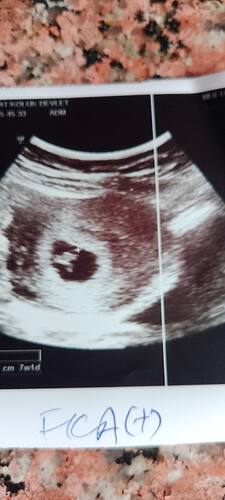

Hep ben tahmin yapıyordum kızlar şimdi ben sizden tahmin bekliyorum Bizim cinsiyetimiz ne teyzeler yorumlarınızı bekliyorum…

Allah nasip ederse inşallah 4. gebeliğim canım